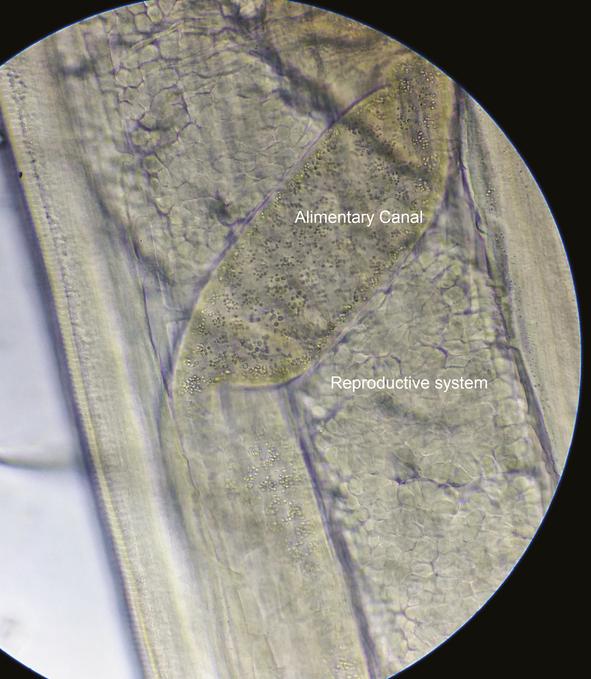

Thelaziasis is an ocular arthropod-borne, zoonotic disease of the eye infecting the conjunctival sac, lacrimal duct, and lacrimal gland caused by a nematode of the genus . We report the first case of human ocular thelaziasis in Nepal in a 6-month-old child from a Rukum district, Nepal. The infant presented with conjunctivitis, and his visual acuity and dilated fundal examination were normal. A total of 6 worms were removed for identification. Collected nematodes were identified based on morphological keys as Thelazia . The patient's symptoms improved after removal of the nematodes.

吸吮线虫病是一种由吸吮线虫属线虫引起的、通过节肢动物传播的眼部人畜共患病,可感染结膜囊、泪道和泪腺。我们报告了尼泊尔首例人类眼部吸吮线虫病病例,患者为一名来自尼泊尔鲁库姆地区的6个月大儿童。该婴儿患有结膜炎,其视力和散瞳眼底检查均正常。共取出6条虫进行鉴定。根据形态学特征,所收集的线虫被鉴定为罗氏吸吮线虫。去除线虫后,患者症状有所改善。